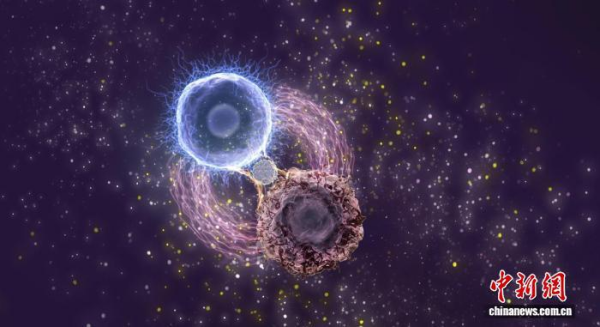

本项研究成果相关示意图。凯发k8过程工程研究所 供图

FACE就像是特制的“双面胶”:在CAR T体外培养过程中,FACE通过结合CD71,稳固地“粘”在CAR T细胞表面;进入体内后,FACE的另一端则牢牢“抓住”白血病细胞表面的CD71,以此促进CAR T细胞对白血病细胞的识别和杀伤,提升CAR T细胞的抗原敏感性。